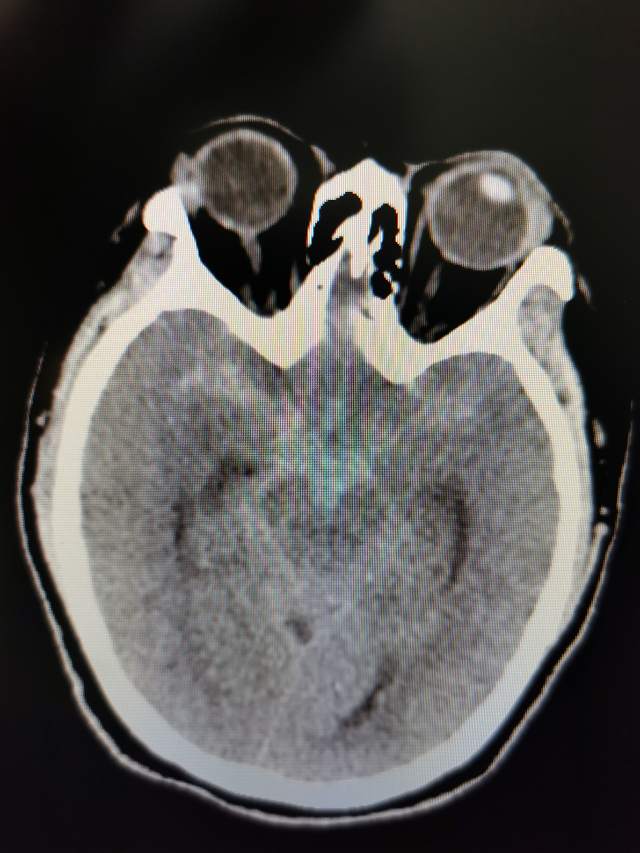

1、立即复查脑CT和DSA:(1)动脉瘤致密栓塞,完全不显影,动脉瘤无增大;(2)出血无增大,排除再出血的可能;(3)整个脑干系统和左侧脑叶呈现明显的低密度,考虑静脉回流障碍所致;(4)脑室引流系统正常引流,未见异常。

2、小插曲出现的原因分析:综合以上现象和脑干的CT低密度表现:术后26小时出现的突发动眼神经麻痹,可能与静脉窦血栓回流障碍引起的动眼神经核麻痹所致,也可能与中脑附近的局部血管痉挛引起所致。